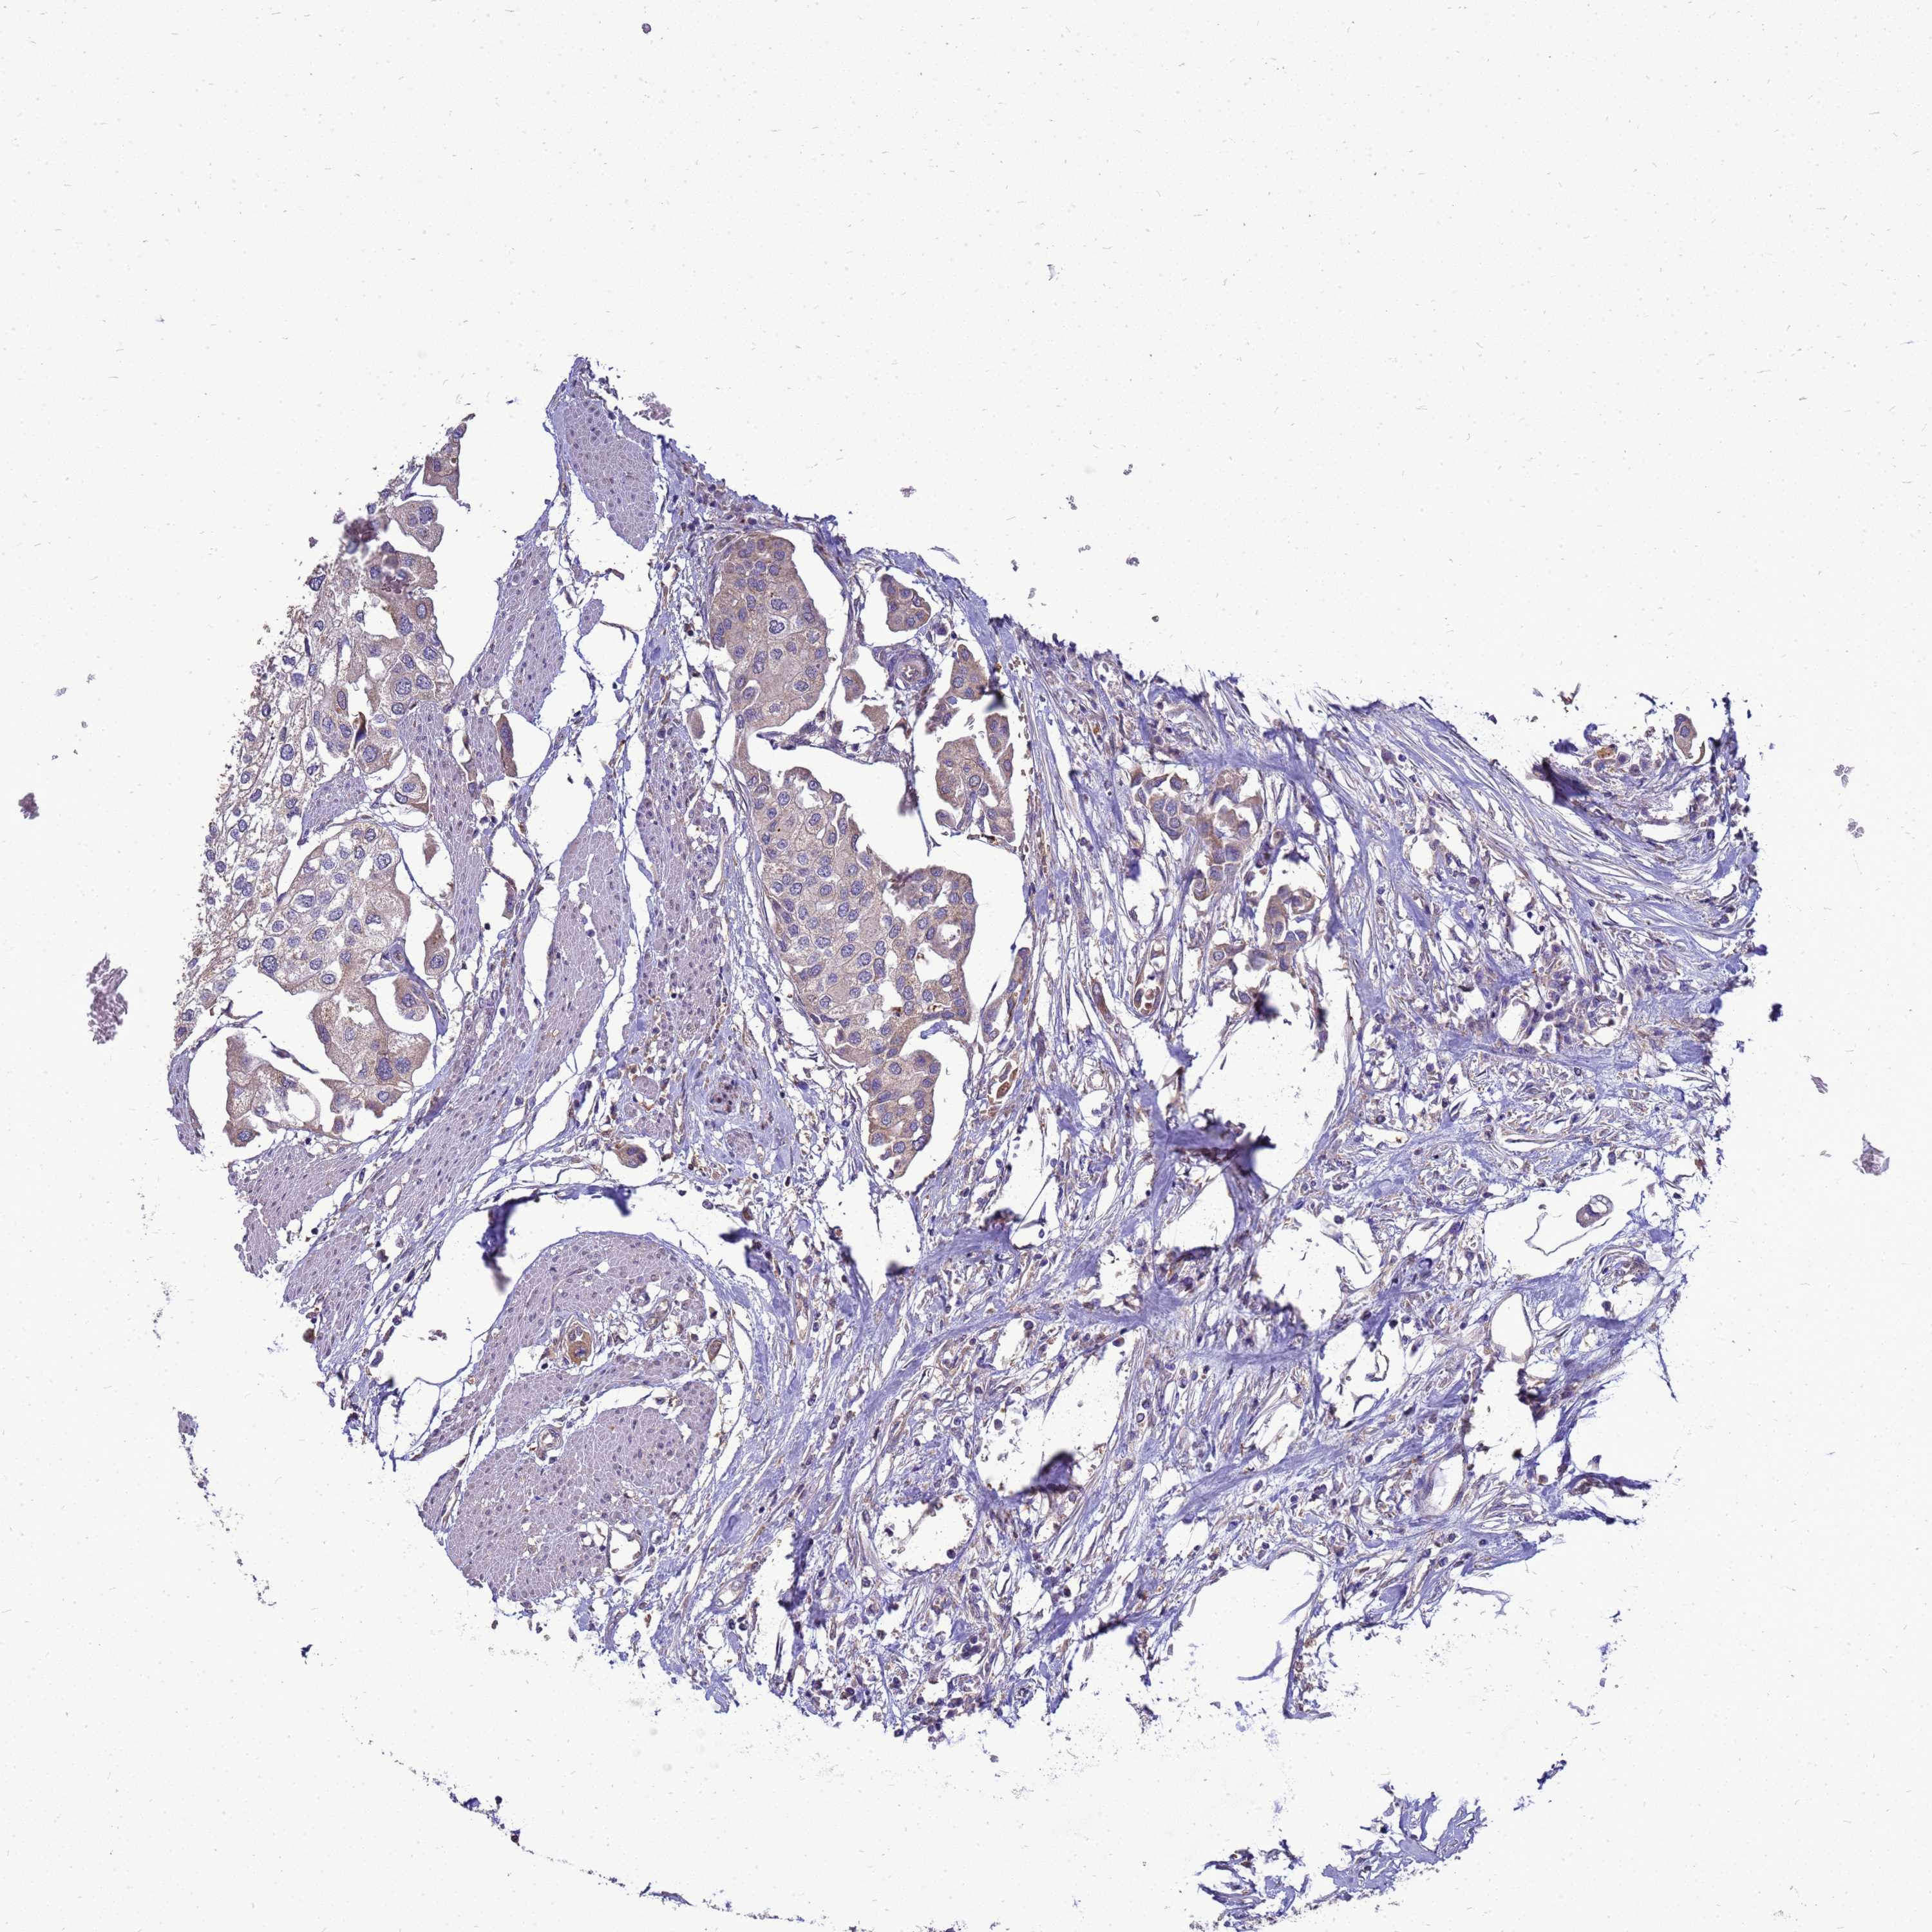

UROTHELIAL CANCER - Protein expressioni

A mouse-over function shows sample information and annotation data. Click on an image to view it in a full screen mode. Samples can be filtered based on level of antibody staining by selecting one or several of the following categories: high, medium, low and not detected. The assay and annotation is described here.

Antibody stainingi

Antibody staining in the annotated cell types in the current human tissue is reported as not detected, low, medium, or high, based on conventional immunohistochemistry profiling in selected tissues. This score is based on the combination of the staining intensity and fraction of stained cells.

Each image is clickable and will lead to virtual microscopy that enables deeper exploration of all samples and also displays staining intensity scores, fraction scores and subcellular localization as well as patient and tissue information for each sample.

Antibody HPA045537

Staining

High

Medium

Low

Not detected

Intensity

Strong

Moderate

Weak

Negative

Quantity

>75%

75%-25%

<25%

None

Location

Nuclear

Cytoplasmic/membranous

Cytoplasmic/membranous,nuclear

Urothelial carcinoma, High grade

Urothelial carcinoma, Low grade

Urothelial carcinoma, NOS